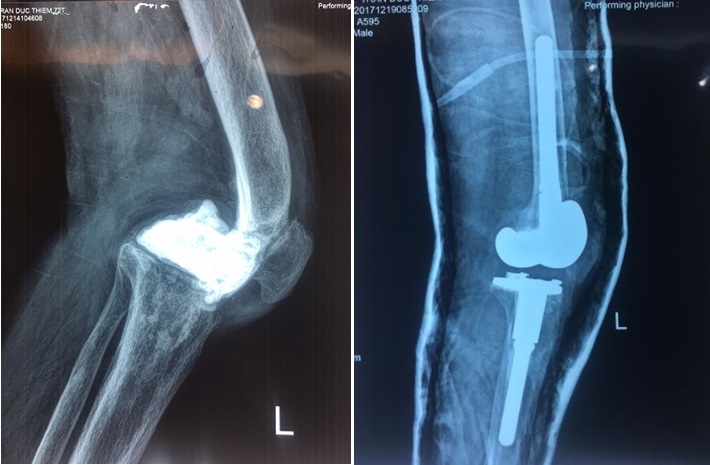

Hình ảnh khớp gối của bệnh nhân trước (trái) và sau (phải) khi thay lại khớp gối lần 2

Rất may, hiện nay trang thiết bị dụng cụ rất phát triển, PGS Khánh cho hay. Dụng cụ thay khớp lần này đặc biệt hơn khớp gối nhân tạo thông thường, đó là nó dài hơn, khoảng 20-30cm , trong khi khớp thông thường chỉ dài từ 5-10cm và giúp cố định vững chắc hơn, đặc biệt có ưu thế với những trường hợp bị khuyết xương nhiều. Để giúp bệnh nhân có khớp gối vững chãi cần loại khớp đặc thù – đặt hàng riêng cho từng người bệnh- đóng sâu vào xương đùi và xương cẳng chân của người bệnh.